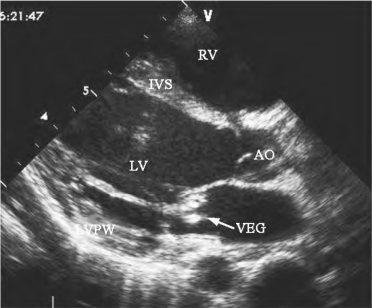

图13-12 二尖瓣赘生物二维超声图

左室长轴切面,显示二尖瓣瓣叶较强回声为赘生物(箭头所示)

(1)二尖瓣叶与腱索连续中断:瓣叶的游离缘与断裂的腱索残端相连(图13-11),断裂的腱索随瓣尖活动呈不规律的异常运动。(2)断裂腱索回声:收缩期左房内显示断裂腱索回声,并在左房内漂浮活动。若为细菌性心内膜炎引起者,可显示瓣尖增厚、断裂腱索增粗、回声增强或附着条状、团状异常回声(图13-12)。